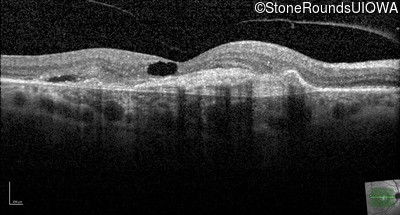

Age at visit: 59 years (Visit 3)